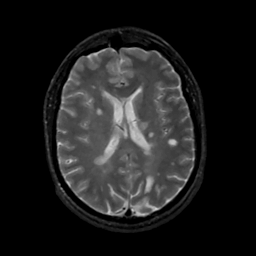

MR Study #14, June 2, 1991 -- Slice #30

[Home][Help][Clinical][Tour 1][Tour 2] Slice 30